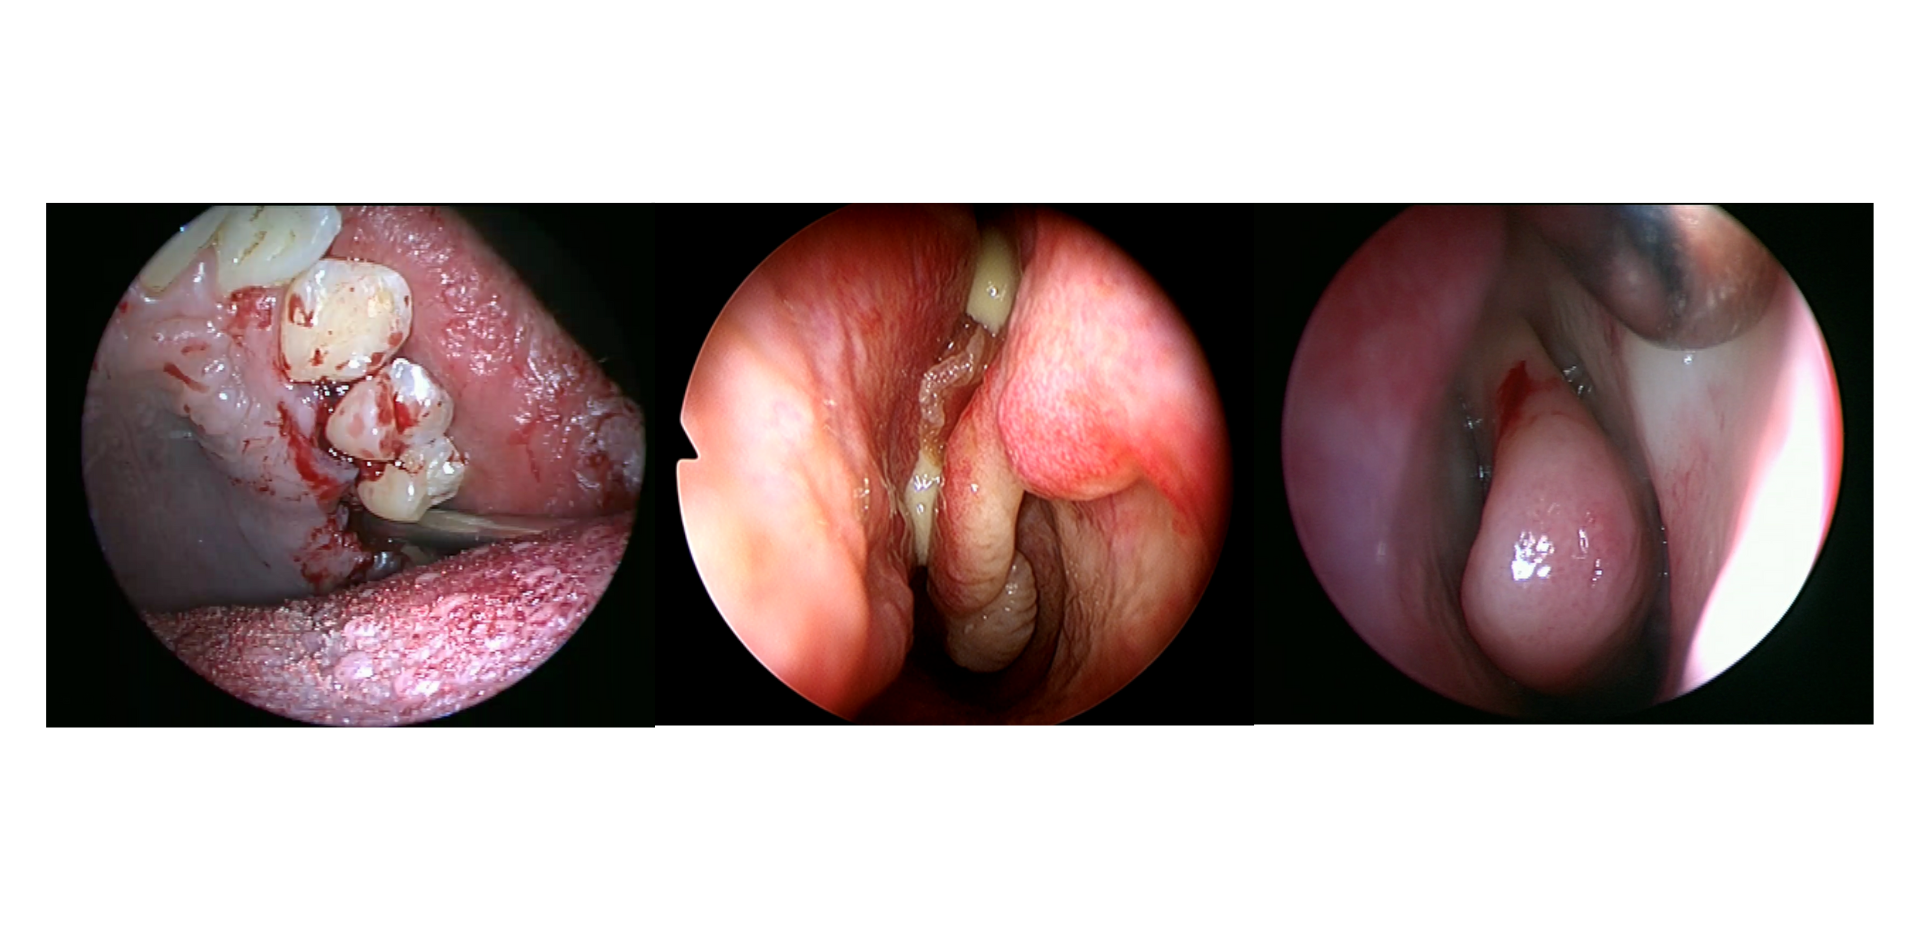

• Patología y cirugía odontológica que puede causar sinusitis maxilar:

- Lesiones de dentales

- Tratamientos endodónticos

- Exodoncias-fístulas oroantrales

- Elevación de seno interna y externa: ventajas e inconvenientes de cada procedimiento en relación con el seno maxilar

- Colocación de implantes: migración de implante al seno maxilar/ perforación de la membrana sinusal...

- Evolución de la sinusitis maxilar odontógena/ relacionada con procedimientos odontológicos: aguda y crónica

- Abordaje vía antrostomía anterior clásica y mínimamente invasiva

- Abordaje endonasal-endoscópico

- Fístula oroantral